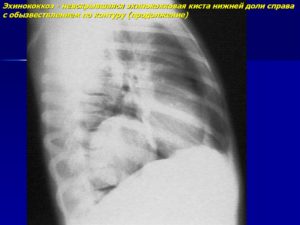

Рентгенологические данные могут иметь определенные различия и зависят от формы и стадии болезни:

- В стадии инфильтрации над поверхностью легких определяется снижение прозрачности легочного рисунка, затем плотность затенения возрастает, и становится виден инфильтрат неправильной формы с размытыми контурами и радиальной тяжистостью по периферии.

- Стадия абсцедирования характеризуется наличием очагов деструкции в пораженном легком с перифокальным воспалением и усилением легочного рисунка в здоровом легком.

- Нередко после прорыва абсцесса в паренхиме легких формируются плевролегочные полости с горизонтальным уровнем жидкости.

Рентгенологическое исследование в ранней стадии выявляет очаговые инфильтраты вокруг бронхов и сосудов, увеличение медиастинальных лимфатических узлов и содружественное поражение ребер или позвонков; характерно уплотнение плевры. Процесс может ограничиваться одним сегментом или захватывать целую долю. Течение болезни длительное, при отсутствии лечения развиваются кахексия и анемизация больных.